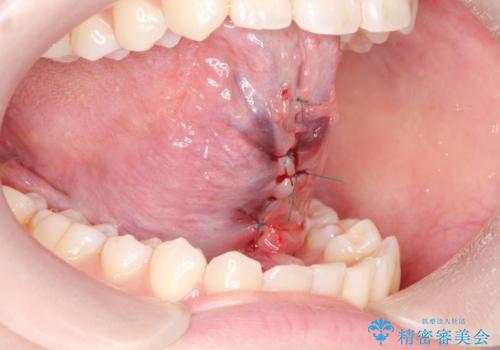

- ら行が言いにくいとの事で来院。舌の動きを舌小帯が邪魔していたので舌小帯の形成術を行いました。

舌小帯の形成手術を行うことにより舌が口蓋に届くようになり

ら行が言いやすくなりました。

舌小帯の手術は当日行うことができます。